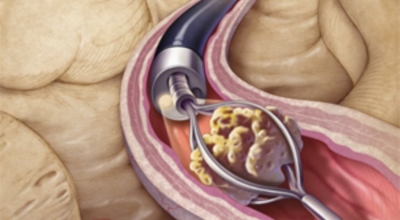

요로결석의 치료방법은 당연히 결석을 없애주는 방법이 최우선인데요 체외쇼크파 쇄석술 이라고 하는 시술을 통해 결석을 자연 배출될 수 있도록 하는 방법이 있답니다. 쇼크파 장치에서 고에너지 쇼크파를 쬐어 결석을 파괴하면, 결석 조각이 알아서 배출될 수 있도록 하는 시술입니다.

입원이 필요치 않은 시술이며 시술 후 1시간이면 바로 일상 회복이 가능하다고 합니다. 물론 더 심한 경우는 내시경 결석 제거술등의 수술을 통해 제거해야 하는 경우도 있답니다. 그러므로 요로결석 증상이 발생한 초기에 빠르게 대응하여 간단한 시술로 결석을 없애는 것이 최우선입니다.